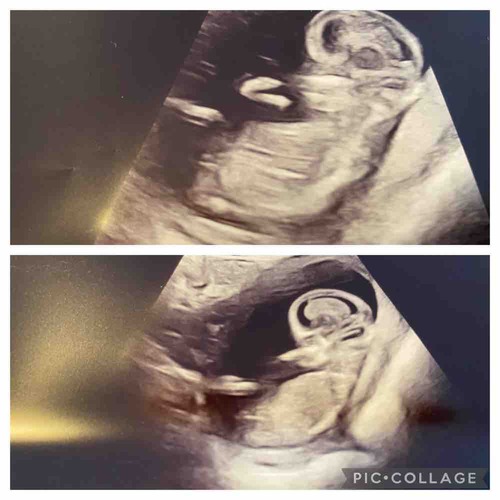

Iemand een idee? 13 weken

Aan 1 kant neig ik naar jongen. Maar kan het niet zeker zeggen want had met dit termijn het toch iets duidelijker verwacht.